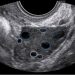

How To Do Ottobre 2022:

Cari soci, questo mese un nuovo video "How to do", dedicato allo studio ecografico della pelvi norma

Guida al Counselling di Ottobre 2022: ridotta riserva ovarica e CFA